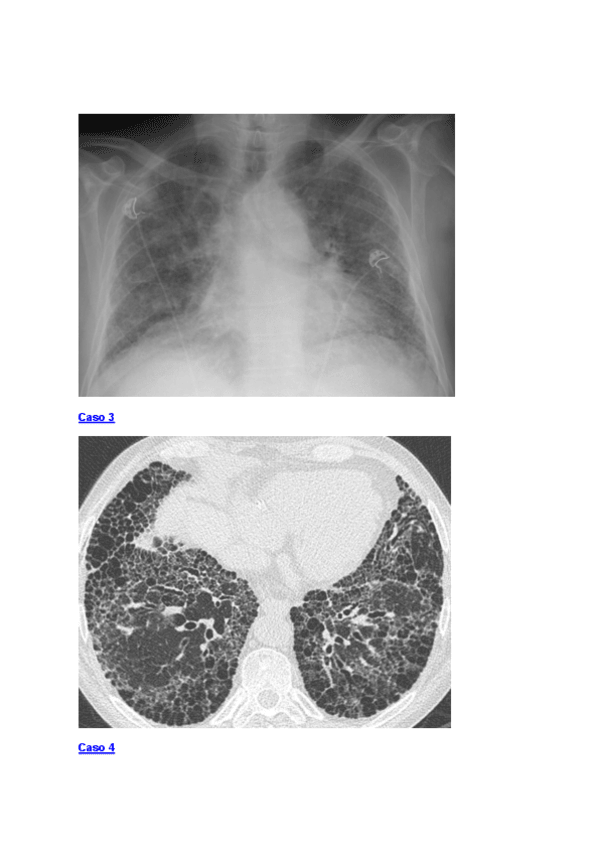

He publicado nuevos examenes de 3º Radiología I: Album-de-casos-de-radiologia-cardiotoracica-para-estudiantes.-Miguel-Souto-Bayarri.-Profesor-de-Radiologia-de-la-USC..pdf

42 páginas